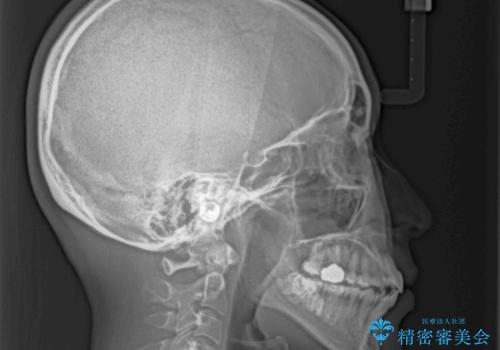

2. 【モニター】急速拡大装置 狭い歯列を拡大してワイヤー装置で短期間治療の治療中